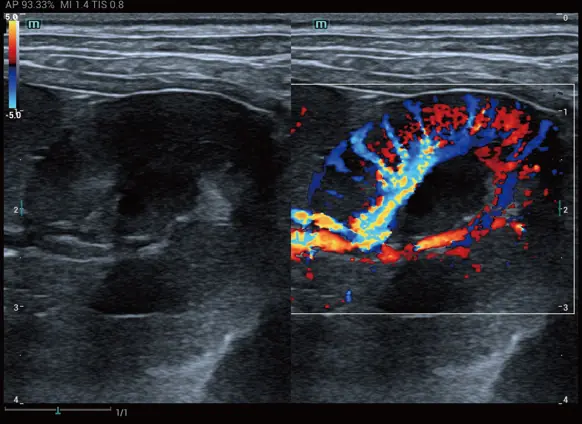

Mikrovasküler veya karmaşık akım paternlerinin görselleştirilmesini geliştiren yenilikçi bir teknolojidir. Mindray Animal’a özgü gelişmiş görüntü işleme algoritmalarıyla, akımın detaylı olarak izlenmesine olanak tanır. HR Flow, hem Renkli Doppler hem de Power Doppler modlarında uygulanabilir.